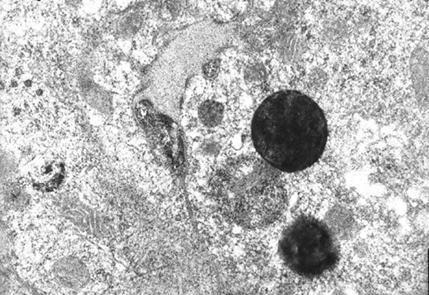

1921年11月,弗莱明在实验过程中,不小心打了个喷嚏,一点鼻腔粘液刚好滴在培养基上。他怎么也没想到,自己的这个举动,竟然帮助科学家研究出了一种药物,在70年内救了上亿人性命,人类寿命也平均提高15年。 弗莱明是个苏格兰乡下娃,小时候家里穷,父亲走得早,基本上就是在山野里“放养”长大的。大自然就是他最好的老师,让他养成了一双特别会观察的眼睛。 20岁那年,他拿到一笔舅舅的遗产,在当医生的哥哥建议下,报考了医学院。毕业后,他跟了一位叫赖特的导师。 真正让他研究方向定型的,是一战。那会儿他跟着老师去法国前线,天天见的都是血肉模糊的伤员。他发现一个特别残酷的事:很多士兵不是死在枪林弹雨里,而是死在了伤口感染上。当时通用的办法是啥?用消毒剂硬灌。结果呢?消毒剂在杀死细菌的同时,也把人体自身的白细胞给干掉了,相当于敌我不分,一通乱杀,伤口感染反而更严重。 这个发现让弗莱明极其震撼。从战场回来后,他就憋着一股劲儿,发誓要找到一种“神药”,它必须得像个精准的狙击手,只杀细菌,不伤人体细胞。这个念头,成了他后半辈子研究的核心目标。 1921年11月,弗莱明正琢磨这事儿呢,结果自己得了重感冒。那天他对着一个培养着细菌的培养皿,没忍住,一个大喷嚏就出去了,一小滴鼻涕不偏不倚落了进去。换做别人,这盘实验材料就废了,得扔。但他不但没扔,还把这个“被污染”的培养皿留了下来。 过了两周,奇迹发生了。他发现培养皿里长满了细菌,唯独滴了鼻涕的那一小块地方,干干净净,细菌全死光了,还形成了一个透明的圈。弗莱明瞬间就兴奋了,他意识到鼻涕里肯定有某种能杀菌的玩意儿! 经过研究,他把这东西命名为“溶菌酶”。为了搞到更多实验材料,据说他满实验室追着同事,用柠檬熏他们的眼睛,就为了收集一点眼泪。 可惜的是,溶菌酶虽然能杀菌,但能力比较弱,对很多厉害的病原菌都没啥用。研究了七年,没啥突破,这事儿就慢慢放下了。 但这就像一次预演,让弗莱明彻底相信,自然界中一定存在着那种他梦寐以求的“精准狙击手”。 1928年的夏天。弗莱明还是老样子,实验室里堆满了各种做完实验没来得及洗的培养皿。他这习惯在别人看来是邋遢,但正是这个“邋遢”,给了第二次偶然一个绝佳的登台机会。 他休假回来,整理桌上那堆“垃圾”时,又发现了一个奇怪的培养皿。里面因为被一种青绿色的霉菌污染了,但他敏锐地注意到,霉菌周围一圈的葡萄球菌也都被杀死了,形成了一个清晰的“无菌圈”。 这一次,弗莱明知道,他可能真的撞大运了。他小心翼翼地把这种霉菌分离出来,发现它分泌的汁液有强大的杀菌能力。因为这种霉菌属于青霉菌属,所以他把这种神奇物质命名为“青霉素”。 弗莱明的发现,在当时几乎无人问津。为啥?因为他遇到了一个巨大的坎儿,他是个细菌学家,不是化学家。他知道青霉素是个宝贝,但他没本事把它从霉菌培养液里大量、稳定地提纯出来。他搞出来的粗提物,杂质太多,效果不稳定,有时候甚至对实验动物有毒。 他写了论文发表,也把菌种送给其他研究机构,但十年过去了,青霉素依然只是躺在论文里的一个名词。弗莱明自己也几乎放弃了。 真正的转机,要等到二战爆发。 战争这个催化剂,再次把“对付伤口感染”这个难题推到了风口浪尖。这时候,牛津大学的两位科学家——霍华德弗洛里和恩斯特钱恩,偶然翻到了弗莱明十年前那篇论文。他们立刻意识到这东西的巨大潜力。 跟弗莱明不同,这俩人一个是病理学家,一个是生物化学家,正好组成了完美的“黄金搭档”。他们重拾了弗莱明的研究,用尽各种化学方法,终于在1940年成功提取出了高纯度的青霉素粉末。提纯后的青霉素,抗菌能力比弗莱明的粗提物强了几千倍。 医学界终于被震撼了。第一个接受治疗的是一个叫艾伯特亚历山大的警察,他因为刮胡子不小心划伤了脸,结果严重感染,满脸流脓,高烧不退,已经快不行了。医生们死马当活马医,给他注射了青霉素。效果立竿见影,他很快就退了烧。可惜的是,当时的青霉素产量实在太低了,所有库存都用完了,也不足以支撑整个疗程,这位警察最终还是去世了。 但这次失败的成功,让全世界看到了希望。当时二战打得正酣,美国政府意识到这东西的战略价值,将其列为仅次于原子弹的最高级别研究项目,投入巨资,动员全国的力量来解决量产问题。 后来青霉素被大量生产出来,送往前线,拯救了无数士兵的生命。战后,它迅速普及到民用领域,肺炎、脑膜炎、败血症这些曾经的“绝症”,一下子变得可以治愈。 1945年,弗莱明、弗洛里和钱恩三人共同获得了诺贝尔生理学或医学奖。